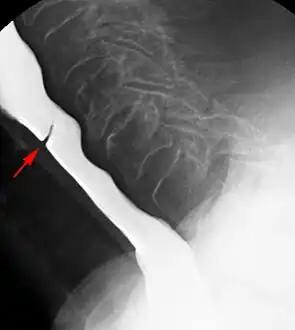

Esophageal webs are thin membranes occurring anywhere along the esophagus.[1]

Esophageal webs are thin 2–3 mm (0.08–0.12 in) membranes of normal esophageal tissue consisting of mucosa and submucosa that can partially protrude/obstruct the esophagus. They can be congenital or acquired. Congenital webs commonly appear in the middle and inferior third of the esophagus, and they are more likely to be circumferential with a central or eccentric orifice. Acquired webs are much more common than congenital webs and typically appear in the cervical area (postcricoid).

The diagnostic test of choice is a barium swallow.